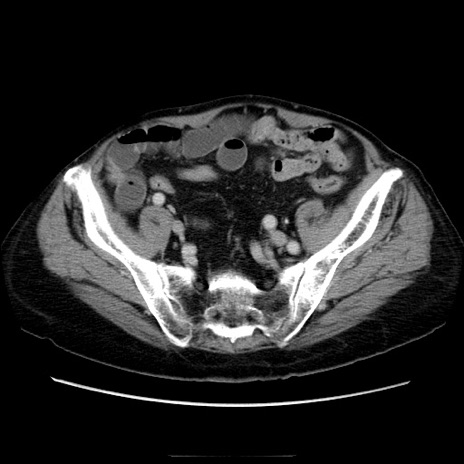

症例21(横断像)

【症例】70歳代男性

【主訴】腹痛

【現病歴】肝硬変・肝細胞癌にてかかりつけの方。約9時間前に食後より腹痛出現。症状が徐々に増悪し、嘔吐出現したため来院。

【既往歴】肝硬変、肝細胞癌(RFA、TACE後)

【身体所見】意識清明、表情苦悶様、BT 36℃、BP 129/78mmHg、P 88bpm、SpO2 97%(RA)、右上腹部から心窩部にかけて圧痛あり、反跳痛なし、筋性防御あり。

【データ】WBC 5800、CRP 0.16